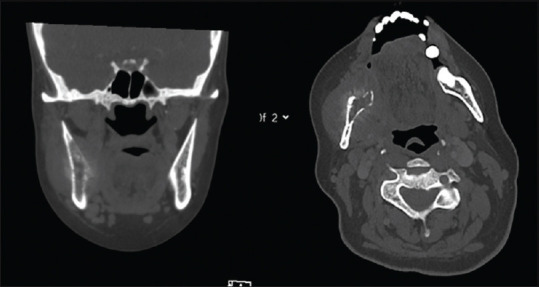

Results: Of 532 patients with head-and-neck cancer between 2008 and 2020, 15 (2.8%) had histologically verified metastatic lesions, of which 53.33% males with a mean age of 69 years. The median time from symptom onset to diagnosis was 17 days (range: 7-60). The mandible was the most common location (40%), followed by the parotid gland (33.33%) and maxilla (13.33%). Adenocarcinoma was the most frequent histology (60%), and half of the patients had extraoral manifestations. Tumour origin was gastrointestinal, lung (33.33% each), prostate (20%) and breast (13.3%). No predilection for tumour type or histology and location were seen. Radiographic features were non-specific, with computed tomography (CT) demonstrating periosteal reaction, bone expansion and lytic lesions and high variability in Positron Emission Tomography (PET) standardised uptake value (minimum: 2.0, maximum: 10.93 and mean: 4.14). Diagnosis led to altered treatment in 60%, more in extraoral than intraoral manifestations (71% vs. 37.5%); 40% received radiotherapy, 20% systemic treatment and none underwent surgery. Over half of the patients passed away within 6 months, median survival was 5 months, shorter in patients with intraoral than extraoral disease (3 vs. 13.2 months, P < 0.05).

Discussion: Maxillofacial metastases have elusive manifestations and often warrant specific treatment. Prospective data should evaluate associations between timely diagnosis and symptomatic improvement and survival.